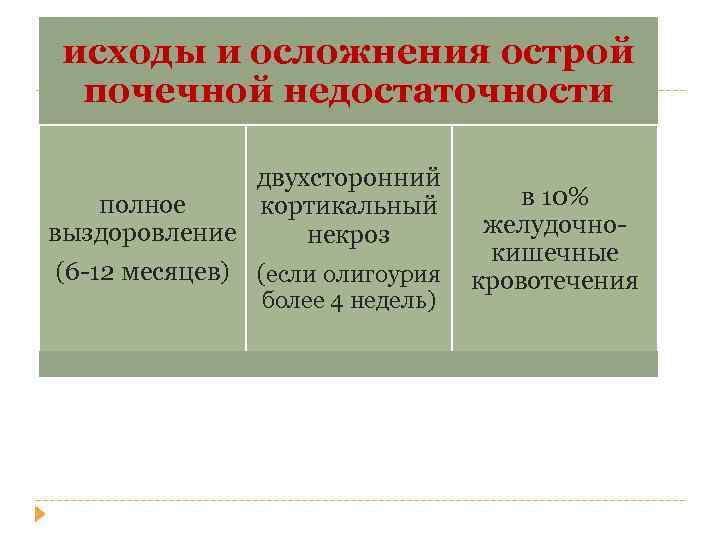

исходы и осложнения острой почечной недостаточности двухсторонний полное кортикальный выздоровление некроз (6 -12 месяцев) (если олигоурия более 4 недель) в 10% желудочнокишечные кровотечения